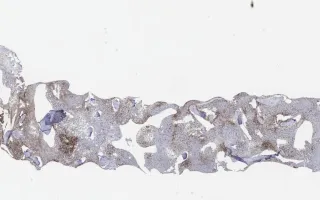

Bone Marrow, Composite B-cell lymphoma, CD3 stain

This slide shows bone marrow biopsy, CD3 stain. See related content for other peripheral blood and bone marrow biopsy stains.